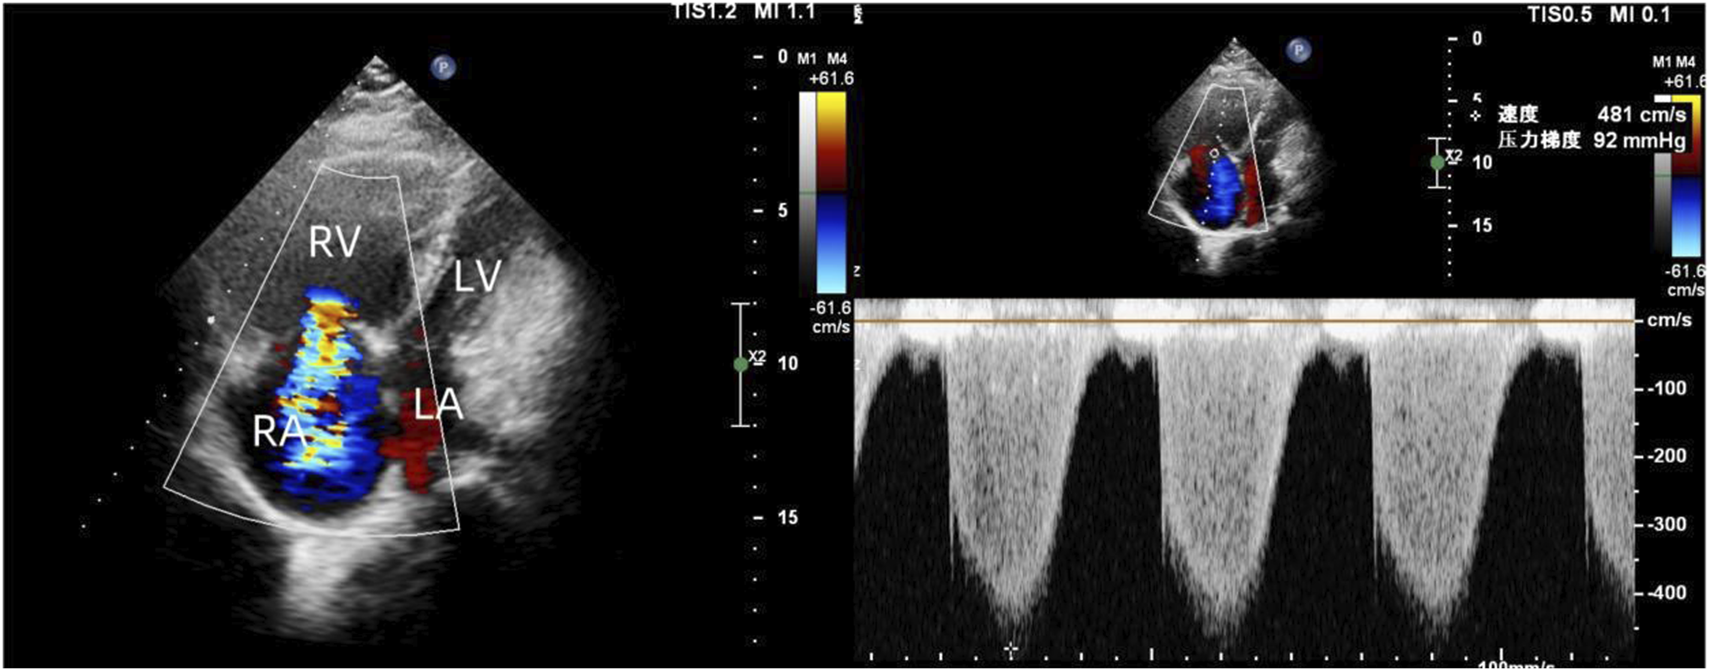

To exclude pulmonary embolism, we performed cardiac MR image (MRI) and pulmonary ventilation perfusion imaging, and revealed pulmonary artery dilatation and right heart enlargement, which may indicate pulmonary arterial hypertension. Transthoracic echocardiography confirmed severe pulmonary hypertension, with an estimated pulmonary artery systolic pressure of 102 mmHg, preserved LVEF (62%), reduced right ventricular wall motion, and severe tricuspid regurgitation (Figure 1). The initial MR and MR angiography of the brain showed no significant abnormalities. A subsequent right heart catheterization at rest confirmed the diagnosis of PAH: the patient had a pulmonary artery pressure of 66/31/43 mmHg, a pulmonary artery wedge pressure of 11 mmHg, a cardiac output of 4.25 L/min and a calculated pulmonary vascular resistance (PVR) of 5.56 Wood units, total pulmonary resistance (TPR) of 7.49 Wood units. Because our patient demonstrated a high pulmonary artery pressure and the cause is unknown. Hence, whole exome sequencing was carried out, and we identified a novel heterozygous mutation in FLNA (c.4754C>T, p.Thr1585Met) and a known heterozygous mutation in MMACHC (c.609G>A, p.Trp203Ter) (Figure 2). In addition, Pedigree analysis of the patient’s son revealed no evidence of these mutations (Figure 2). Following multidisciplinary discussion and being fully informed about the risks to the patient, the patient was initiated on PAH-specific therapy, including tadalafil (20 mg daily), macitentan (10 mg daily), and pulmonary artery denervation (PADN) treatment (Figure 3). Her therapeutic regimens were continued for the next 2 years with periodic follow-up. The timeline of treatment course for this patient was shown in (Table 1). Surprisingly, she showed a satisfactory clinical response to PAH therapies, her disease symptoms were alleviated, and no sign of heart failure was observed during the follow-up period.

FIGURE 1

Transthoracic echocardiography revealed enlarged right heart, reduced right ventricular wall motion, and severe tricuspid regurgitation.